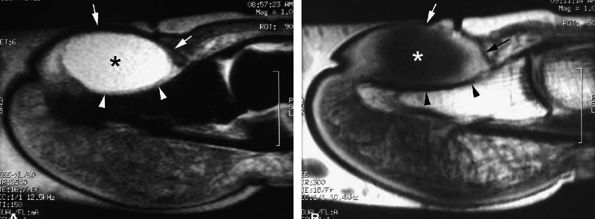

FIGURE 11.34 ● Complete rupture of the central slip of the extensor tendon on sagittal (A) and axial post-enhanced T1-weighted images at the level of the PIP joint space (B) and the distal third of the proximal phalanx (C). There is distal avulsion of the central slip with a tendon gap (arrows) and limited retraction. The proximal end is thickened and shows signal heterogeneity (asterisk).